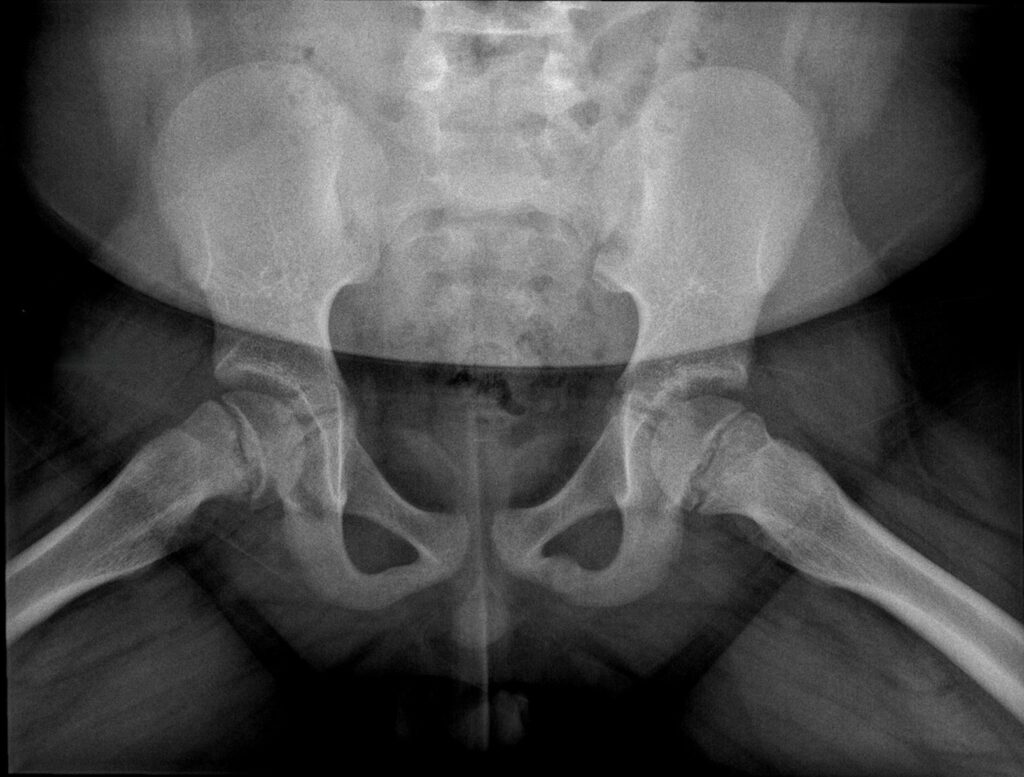

AP view of the hips

‘Melting ice cream sign’: Femoral head (epiphysis) slipping off the femoral neck (metaphysis) though the growth plate (physis) like an ice cream melting from the cone.

He says, the recommended imaging is an anterior-posterior pelvic view which shows malalignment and widening of the growth plate and a frog-leg lateral view, the most sensitive for detecting early or subtle slips.’

‘Key radiological signs,’ says Dr Greyling are:

- Widening of the growth plate

- Loss of height of the femoral head

- Loss of alignment of the anatomical lines that intersect with the femoral head

- ‘Melting ice cream sign’ slipping off the femoral neck at the growth plate (epiphysis).